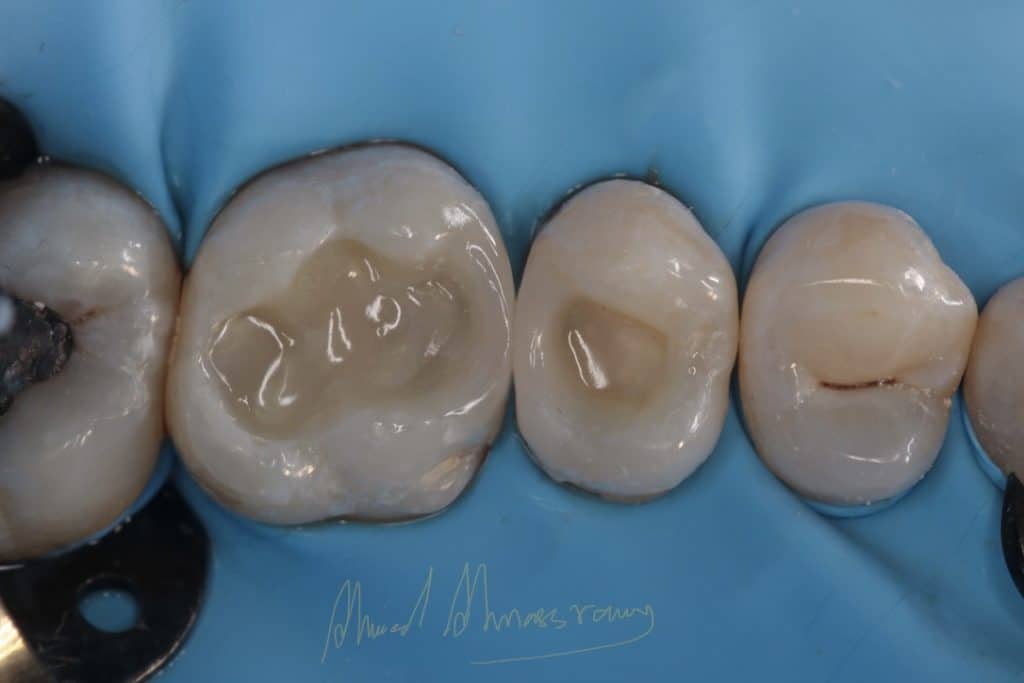

sixth generation se bond

finishing and polishing (enhance kit from dentsply)